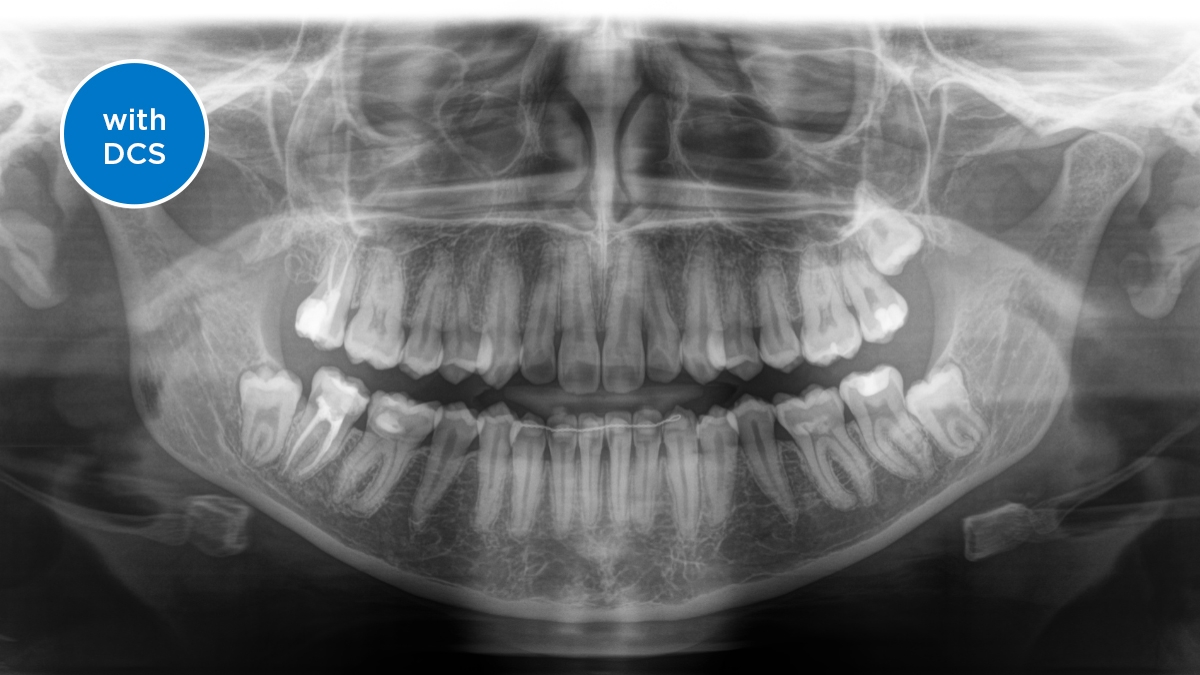

Senzor de conversie directă (Direct Conversion Sensor - DCS): Detalii ale unei imagini clare

Senzorul de conversie directă (DCS) a revoluționat standardele de imagistică panoramică. Razele X sunt convertite direct în semnale electrice. Astfel, nu se înregistrează pierderi de semnal din cauza conversiei luminii, așa cum se întâmplă în cazul sistemelor convenționale. Rezultatul: imagini cu un nivel extrem de ridicat de claritate și contrast – chiar și la o doză foarte scăzută. Pentru diagnostice clare și tratamente țintite.

Imaginile arată radiografii cu și fără tehnologia DCS. Analizați imaginile și observați plusul pe care senzorul DCS îl aduce calității imaginii.